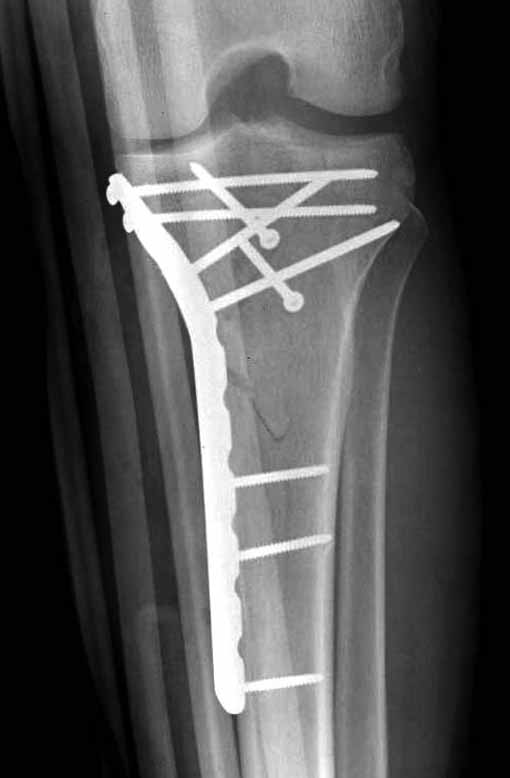

Двухколоннный перелом тибиал плато с вовлечением проксимального диафиза. Внутрисуставной компонент без смещения, и такой перелом можно лечить любым из описанных методов, о которых говорят наши коллеги.

Удобно аппаратом Илизарова или интрамедуллярным гвоздем. Гвозди не так сложно, как пугают, тем более Александр готов помощь с методичкой. Сперва надо установить компрессирующие шурупы на мыщелки. Давно отказались в пользу 3.5-4.0 мм кортикальных вместо толстых спонгиозных, потому что не доказаны преимущества толстых шурупов. Тонкие шурупы в субхондральной зоне смотрятся намного элегантнее, чем толстые 6.5.

Это мероприятие превращает перелом в простой диафизарный, который легко можно фиксировать гвоздем. Шурупы надо установить сзади предполагаемого места введения гвоздя.

Как понял, аппарат Илизарова не рассматривается предпочтительным для фиксации методом, хотя на фоне отека было бы идеальным для данного перелома. Для пластины требуется идеальная кожа, иначе наличие “суперсовременных имплантов” не поможет, и могут развиться серьезные осложнения.

В основном пластины рассчитаны на латеральную поверхность, потому что с латеральной стороны больше мягкотканая подушка, а также через латеральную колонну проходит ось конечности, что немаловажно в удержании оси от деформации.

Для изолированных переломов медиального тибиал плато, фиксацию можно провести “медиальной пластиной”. Некоторые компании, например Smith & Nephew делают медиальные и медиально-задние пластины, но они мягкие, и легко можно создать нужный контур. Жесткость создается за счет фиксации жесткими пластинами, например экстра артикулярной пластиной для дистального плеча от Synthes. Медиальный доступ тоже не из легких, надо работать между pes and medial gastroc.

Частая ошибка, когда фиксацию двух колонного перелома проводят одиночной пластиной, т.е с одной стороны, и такая фиксация не удерживает, происходит вторичноое смещение. Необходимо нейтрализовать второй пластиной или дополнительным наружным фиксатором.

Если у вас, кроме пластины, нет другого альтернативного варианта, тогда, учитывая мягкотканые проблемы с наружной стороны, я бы рекомендовал операцию делать в два этапа. Преимущества, сперва репозиция и фиксация перелома с медиальной стороны, а затем, после улучшения состояния мягких тканей, зафиксировать с латеральной стороны. Современные пластины имеют латеральный Jig для перкутанных мини доступов.

В приложении этапы фиксации Both Column Fx и пластиной Synthes для плеча при переломе медиального мыщелка.